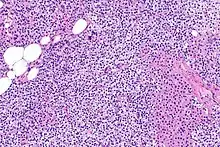

Hyperparathyroidism, in general, is caused by either tumorous growth in one or more parathyroid glands or a prolonged decrease in blood calcium levels or hypocalcaemia which in turn stimulates the production of parathyroid hormone release from the parathyroid gland.[10][11] The parathyroid gland is located beside the thyroid gland in the neck, below and in front of the larynx and above the trachea. It is composed of four glands in total that monitor blood calcium levels via the calcium sensing receptors, a g-coupled protein receptor.[12] The parathyroid glands main role is calcium homeostasis.[13][12] Histologically, these glands are composed of chief cells and oxyphil cells with the chief cell primarily responsible for the storing and release of parathyroid hormone. These cells are arranged in a pseudo-follicular pattern similar to the thyroid follicles. Keratin staining is used to image the parathyroid hormone granules.[9][14]

Primary hyperplasia of the parathyroid gland, results from both hypocalcaemia and increased phosphate levels by decreasing expression of calcium sensing receptors and vitamin D receptors at the parathyroid gland.[8][4] These decreases in receptor expression lead to hyperfunctioning of the parathyroid. Hyperfunction of the parathyroid gland is thought to exacerbate primary hyperplasia which evolves further to a secondary more aggressive hyperplasia. Histologically, these hyperplasic glands can be either diffuse or nodular.[24] Primary hyperplasia, usually resulting in diffuse polyclonal growth is manly related to reversible secondary hyperparathyroidism. Secondary hyperplasia of the parathyroid gland is more often a nodular, monoclonal growth that sustains secondary hyperparathyroidism and is the catalyst in the progression to tertiary hyperparathyroidism. Nodular hyperplastic glands in tertiary hyperparathyroidism are distinctly larger in both absolute size and weight up to 20-40-fold increases have been reported.[25][26][24]

Parathyroid glands are normally composed of chief cells, adipocytes and scattered oxyphil cells.[27][14] Chief cells are thought to be responsible for the production, storage and secretion of parathyroid hormone. These cells appear light and dark with a prominent Golgi body and endoplasmic reticulum. In electron micrographs, secretory vesicles can be seen in and around the Golgi and at the cell membrane. These cells also contain prominent cytoplasmic adipose.[27][14] Upon onset of hyperplasia these cells are described as having a nodular pattern with enlargement of protein synthesis machinery such as the endoplasmic reticulum and Golgi. Increased secretory vesicles are seen and decreased intercellular fat is characteristic.[27][24] Oxyphil cells also appear hyperplasic however, these cells are much less prominent.